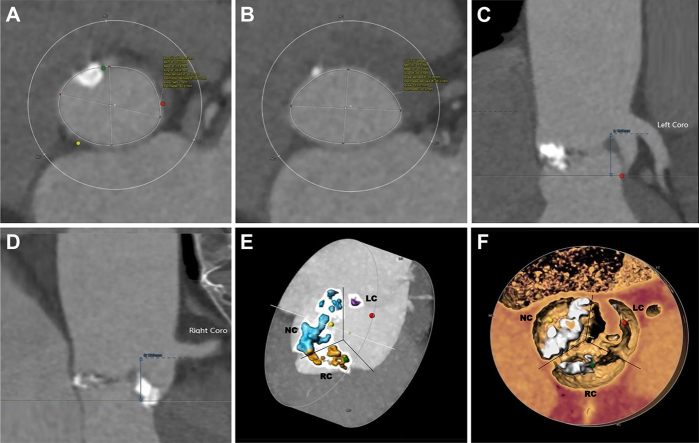

Figure 1.

Preprocedure Computed Tomography

(A) The annular diameter (area) was 26.3 mm. (B) The outflow tract diameter (area) was 25.6 mm. (C) The left coronary opening height was 16 mm. (D) The right coronary opening height was 17 mm. (E, F) A significant stenotic type 1 bicuspid valve (non–right coronary cusp fused) with bulky, asymmetric leaflet calcification.

This patient had severe eccentric calcific stenosis of the aortic valve combined with moderate-to-severe regurgitation (Videos 1 and 2). The preprocedure left ventricular end-diastolic and systolic diameters were 54 and 36 mm, respectively. The peak transvalvular flow velocity and mean pressure gradient were 4.5 m/s and 81 mm Hg, respectively (Supplemental Figures 1 and 2). Preoperative computed tomography (CT) demonstrated a significant stenotic type 1 bicuspid valve (non–right coronary cusp fused) with bulky asymmetric leaflet calcification (Figure 1).